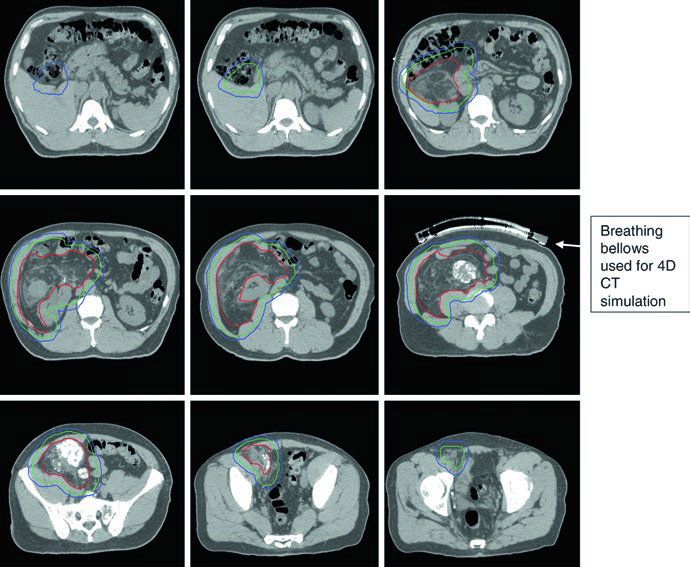

El edema peritumoral en sarcomas de extremidades puede alcanzar extensiones notables. Un caso ilustrativo del texto describe un mixofibrosarcoma grado 2 de muslo lateral con edema peritumoral masivo extendiéndose superior e inferiormente, resultando en un PTV de 42 cm — superando la capacidad máxima de campo para técnicas de isocentro único en la mayoría de los aceleradores lineales.

La solución empleada fue una técnica IMRT de doble isocentro, con los isocentros posicionados estratégicamente cerca del centro de cada subvolumen adyacente y cooptimizados para garantizar cobertura uniforme del PTV en la zona de unión. Esta situación refuerza la importancia de mapear completamente el edema en la RM T2 antes de la simulación: subestimar la extensión del edema compromete la cobertura terapéutica. La RM sagital resulta particularmente valiosa para delimitar la extensión craneocaudal.

La simulación 4DCT se recomienda especialmente en el retroperitoneo, donde el movimiento respiratorio puede desplazar el tumor y los órganos adyacentes. Las calcificaciones intratumorales multifocales, cuando están presentes, sirven como excelentes sustitutos de fiduciales para la guía diaria de imagen en IMRT dirigida. El desplazamiento intestinal por el propio tumor es, paradójicamente, una ventaja del enfoque preoperatorio: con el tumor todavía in situ, las asas intestinales quedan naturalmente alejadas del campo de tratamiento.